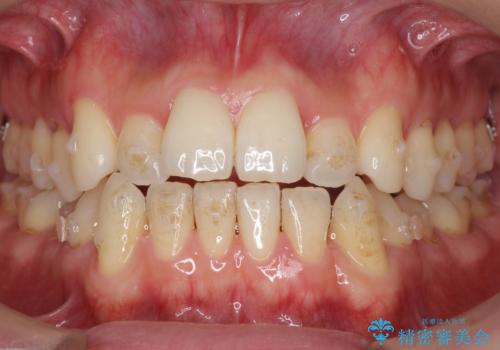

- 受け口を主訴に来院。

前歯の反対咬合でしたが、かみ合わせが、下顎が大きく前方にずれていました。

引っ込んでいる前歯の前方に下の犬歯が深く咬み込んでおり、また、奥歯のかみ合わせも受け口方向にずれ、骨格性の反対咬合も少々ありました。

上の前歯を前方に出すだけでは治療ができないため、ミニスクリューを用いて下の奥歯を後ろに送っています。

また、下の前歯を0.3mmずつIPRしています。